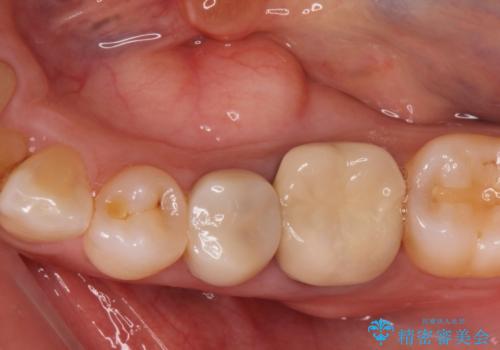

- 寝ている間に歯ぎしりをしている気がするとの事で来院。

過去にナイトガードを使用したことがあったが穴が空いてしまったそうです。

保険のナイトガードよりも穴が空きにくいナイトガードのご案内をしてフラットタイプナイトガード(自費でのご案内)

を作製することになりました。

ナイトガードを使用することによって歯がすり減る(寝ている時の歯ぎしりなど)事を防いでくれます。

保険のナイトガードよりも厚くて硬いので壊れたり割れたりする心配がありません。